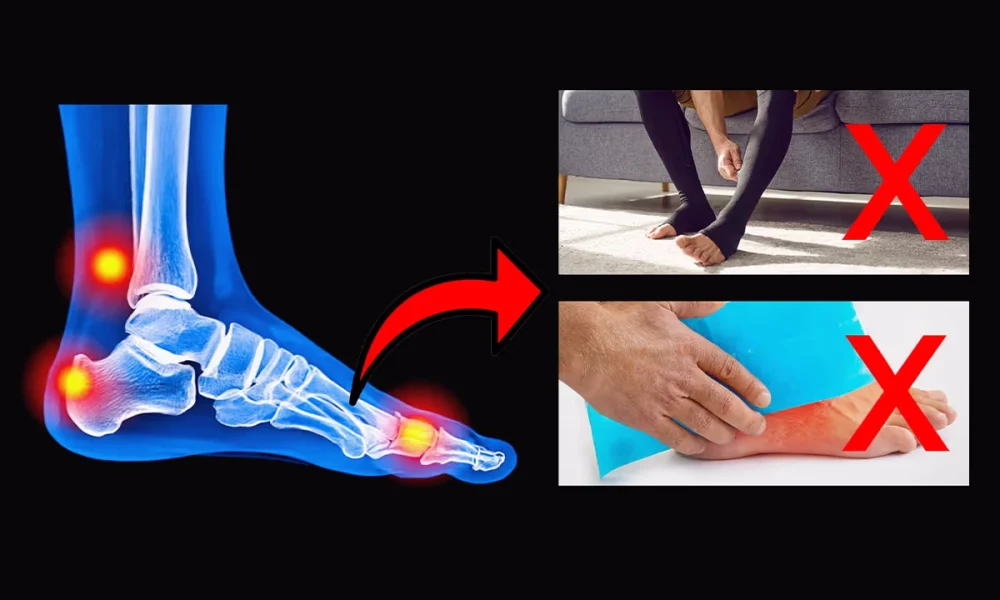

Lo intenté todo — pero nada me dio un alivio real

Sentía que ya había probado casi todo.

Gasté una fortuna en plantillas ortopédicas personalizadas que no me dieron el confort que esperaba. Probé todo tipo de cremas herbales — sin resultados.

Compré zapatos “cómodos” muy caros, que solo empeoraron las cosas. Ni siquiera los ejercicios de estiramiento ayudaban; algunos días apenas podía caminar.

Parecía estar atrapado en un ciclo de soluciones temporales que nunca abordaban la raíz del problema.

Este experto desarrolló una teoría: en muchos casos, el problema no está en los propios nervios, sino en lo que les ocurre.

Él sugería que los nervios estaban, literalmente, “muertos de hambre”.

Mi amigo me explicó la teoría del experto: con el tiempo, la circulación en nuestros pies puede deteriorarse. Los diminutos vasos sanguíneos que alimentan las terminaciones nerviosas se pueden estrechar, ralentizando el flujo de sangre rica en oxígeno.

Privados de oxígeno, los nervios empiezan a fallar y a enviar señales erróneas: ardor, hormigueo… y al final, se vuelven insensibles, provocando entumecimiento.